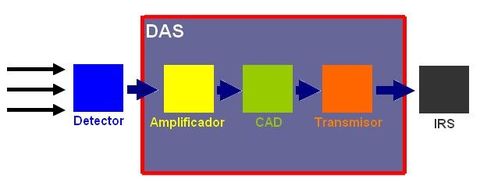

DAS ( Data acquisition system)